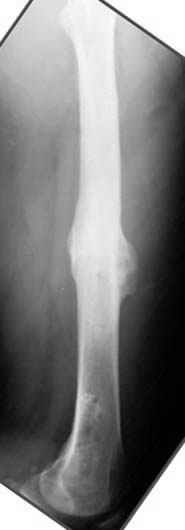

Несколько снимков из моей коллекции, чтобы разьяснить, почему мы до сих пор делаем различные варианты остеотомии.

На рисунке N1 предоперационный план лечения ложного сустава шейки бедра- линия ложного сустава, угол и направление введения импланта, клиновидная остеотомия в градусах и миллиметрах, второй снимок после коррекции, расчет, на сколько удлиняется конечность и размеры импланта;

N3 рисунок окончательный снимок, после операции моя рентгенограмма должен выглядеть примерно как эта картина. На N4 снимке клин перед удалением; N5 послеоперации 3 нед.; N6 окончательная рентгенограмма.

(доложен в Ст. Петербурге 2003 и в Москве 2004)

варус при проксимальном отделе 95 градусной пластиной.

пластическая модель; и коррекция бедра аппаратом Илизарова.